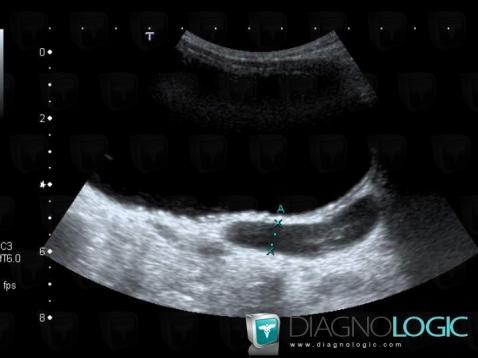

Duplicated collecting system, Ureter, X rays

Here is the specific information in the key image above:

- Diagnosis Duplicated collecting system, Location(s) Ureter, with gamuts